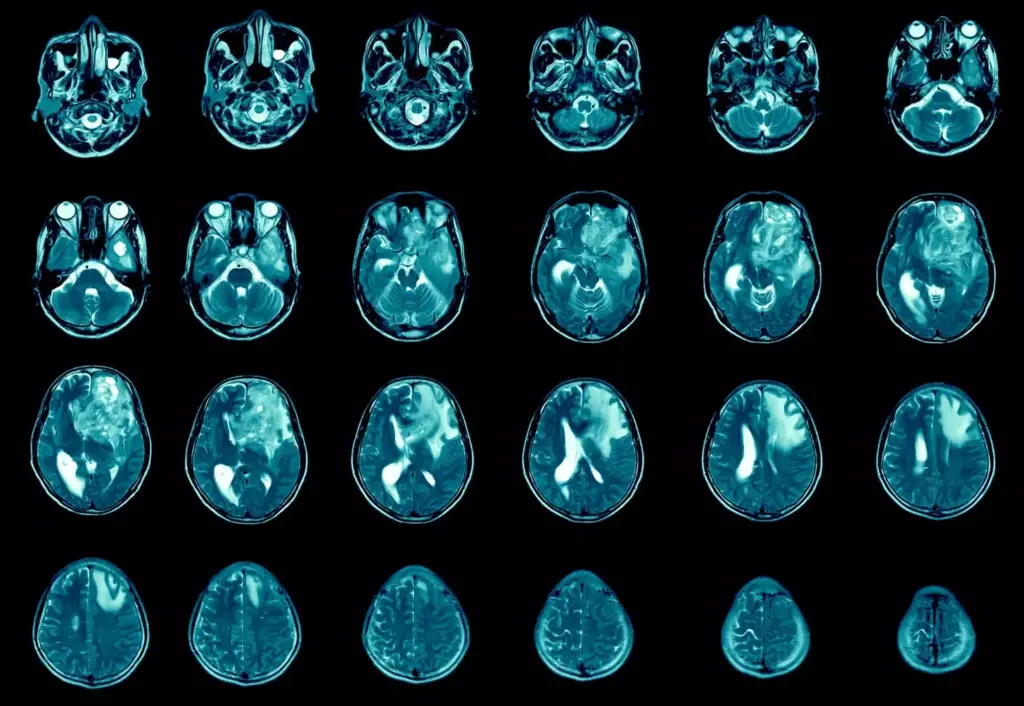

Advanced imaging is vital for diagnosing brain tumors. We use the latest technologies to see the tumor and its surroundings in great detail.

Some advanced imaging methods we use are:

| Imaging Modality | Key Features | Clinical Utility |

|---|---|---|

| MRI (Magnetic Resonance Imaging) | High-resolution soft tissue imaging | Detailed tumor visualization, tumor-brain interface assessment |

| CT (Computed Tomography) Scan | Rapid imaging, calcification detection | Emergency situations, bony structure evaluation |

| PET (Positron Emission Tomography) | Metabolic activity assessment | Tumor grading, treatment response evaluation |

“The integration of advanced imaging techniques has revolutionized the field of neuro-oncology, enabling more accurate diagnoses and personalized treatment plans.”

We use MRI and CT scans to make sure the plan fits each patient’s brain perfectly. This way, we can make sure the surgery is as safe and effective as possible.

Intraoperative MRI lets surgeons see how the surgery is going in real-time. It shows how much of the tumor is being removed. This helps surgeons adjust during the surgery to remove more tumor safely.

To diagnose a brain tumor, we do a thorough evaluation. This includes neurological exams, MRI scans, and biopsy procedures. Our team at Liv Hospital uses the latest technology for accurate diagnoses.

Intraoperative MRI is key in brain tumor surgery. It allows for real-time monitoring and improves surgical precision. This technology helps our neurosurgeons at Liv Hospital achieve the best results.